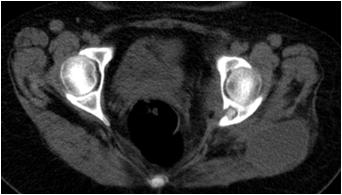

CT scan axial images of a 33 year old lady presenting with pain and swelling in left gluteal region.

1) What is the diagnosis? 2) Name the sign shown in the image. 3) What are the differential diagnosis of this lesion?

Answers:

1) Osteolytic lesion with sequestrum in posterior left acetabulum along with collection in gluteal region. Biopsy was performed from the lesion and gluteal collection was aspirated - the results of which confirmed tubercular osteomyelitis. 2) Bony sequestrum – It refers to calcification within lucent lesion, often completely separated from surrounding bone. Pathologically sequestrum refers to a piece of devitalised bone with necrosis and resorption that has been separated from its surrounding bone. 3) Bony sequestrum is often present in osteomyelitis and skeletal tuberculosis. The other conditions which mimic sequestrum are eosinophilic granuloma, lymphoma, metastasis and malignant fibrous histiocytoma. Some primary bone tumors like osteoid osteoma can also mimic bony sequestrum.